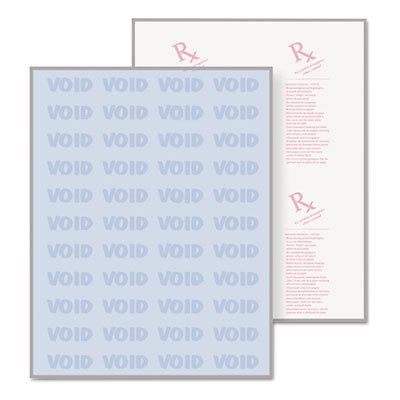

DocuGard Security Paper, 8-1/2 x 11, Blue, 500/Ream, Sold as 1 Ream